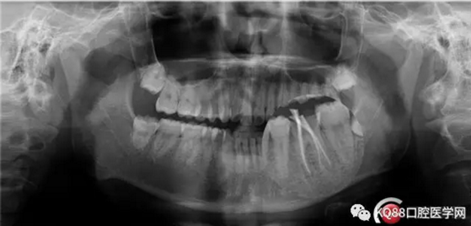

X-ray:36根尖云霧狀低密度影,根分叉未見異常。

診斷:36慢性增生性牙髓炎。

1.png

2.png

處理前牙齒情況,可以看到大量腐質(zhì)和息肉。